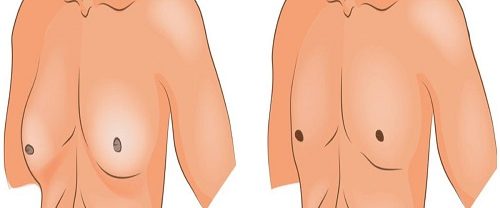

Meme Küçültme Ameliyatı Nedir? Meme küçültme ameliyatı, tıbbi olarak “reduksiyon mammaplasti” olarak da adlandırılır ve genellikle büyük, ağır veya sarkık göğüslerden şikayetçi olan kadınlar arasında popüler bir cerrahi prosedürdür. Bu ameliyat, göğüslerin boyutunu azaltmak, şeklini düzeltmek ve genellikle bu durumun neden olduğu fiziksel rahatsızlıkları gidermek için yapılır. Bu ameliyat genellikle aşağıdaki durumlarda düşünülür: Fiziksel Rahatsızlık:…

Meme Dikleştirme Ameliyatı Meme dikleştirme ameliyatı, memelerin sarkması veya gevşemesi durumunda uygulanan cerrahi bir prosedürdür. Genellikle doğum, emzirme, aşırı kilo kaybı veya yaşlanma gibi faktörler nedeniyle meme dokusunun elastikiyetini kaybetmesi sonucunda memelerdeki sarkmanın düzeltilmesi amacıyla yapılır. Ameliyat Türleri: Meme dikleştirme ameliyatı, genellikle üç farklı teknikle gerçekleştirilir: Geleneksel Meme Dikleştirme: Bu yöntemde, meme dokusu yeniden şekillendirilir…

Meme Büyütme Ameliyatı Nedir? Meme büyütme ameliyatı, kadınların meme hacmini artırmak için cerrahi bir prosedürdür. Bu ameliyat sırasında, meme implantları kullanılarak meme dokusunun hacmi ve şekli artırılır. Meme büyütme ameliyatı genellikle estetik nedenlerle tercih edilir ve kadınların memelerinin boyutunu artırmak, simetrisini düzeltmek veya meme dokusunun kaybını telafi etmek için yapılır. Meme Büyütme Ameliyatı Nasıl Yapılır?…

Meme Göğüs Estetiği Nedir? Meme Göğüs Estetiği, meme görünümünü iyileştirmek veya değiştirmek için cerrahi veya cerrahi olmayan prosedürlerin kullanıldığı bir tıbbi uygulamadır. Bu prosedürler genellikle kadınların meme boyutunu artırmak, şekil vermek, simetrilerini düzeltmek veya meme dokusunu yeniden yapılandırmak için yapılır. Ancak, bazı durumlarda erkekler de meme estetiği prosedürlerine başvurabilirler. Meme Göğüs Estetiği, cerrahi ve cerrahi…